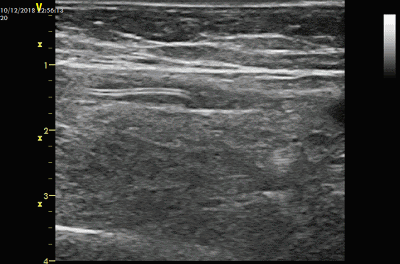

经过溶栓,有的AVG血流恢复较好,有的则恢复较弱血流,也有的血流仍然未恢复。

但即使未恢复,溶栓造成的以上变化也是有助于下一步的球囊碎栓治疗。

另外,血栓中“通道”的出现不仅可以使得血流初步恢复,而且在接下来的球囊扩张时可以成为一个“泄压”通道,即在球囊扩张时对两侧血栓的挤压产生的占位效应和压力可以通过该通道减轻,减少两侧血栓的移位,这一点在动脉吻合口尤为重要,减少血栓脱落进入动脉远端的风险。